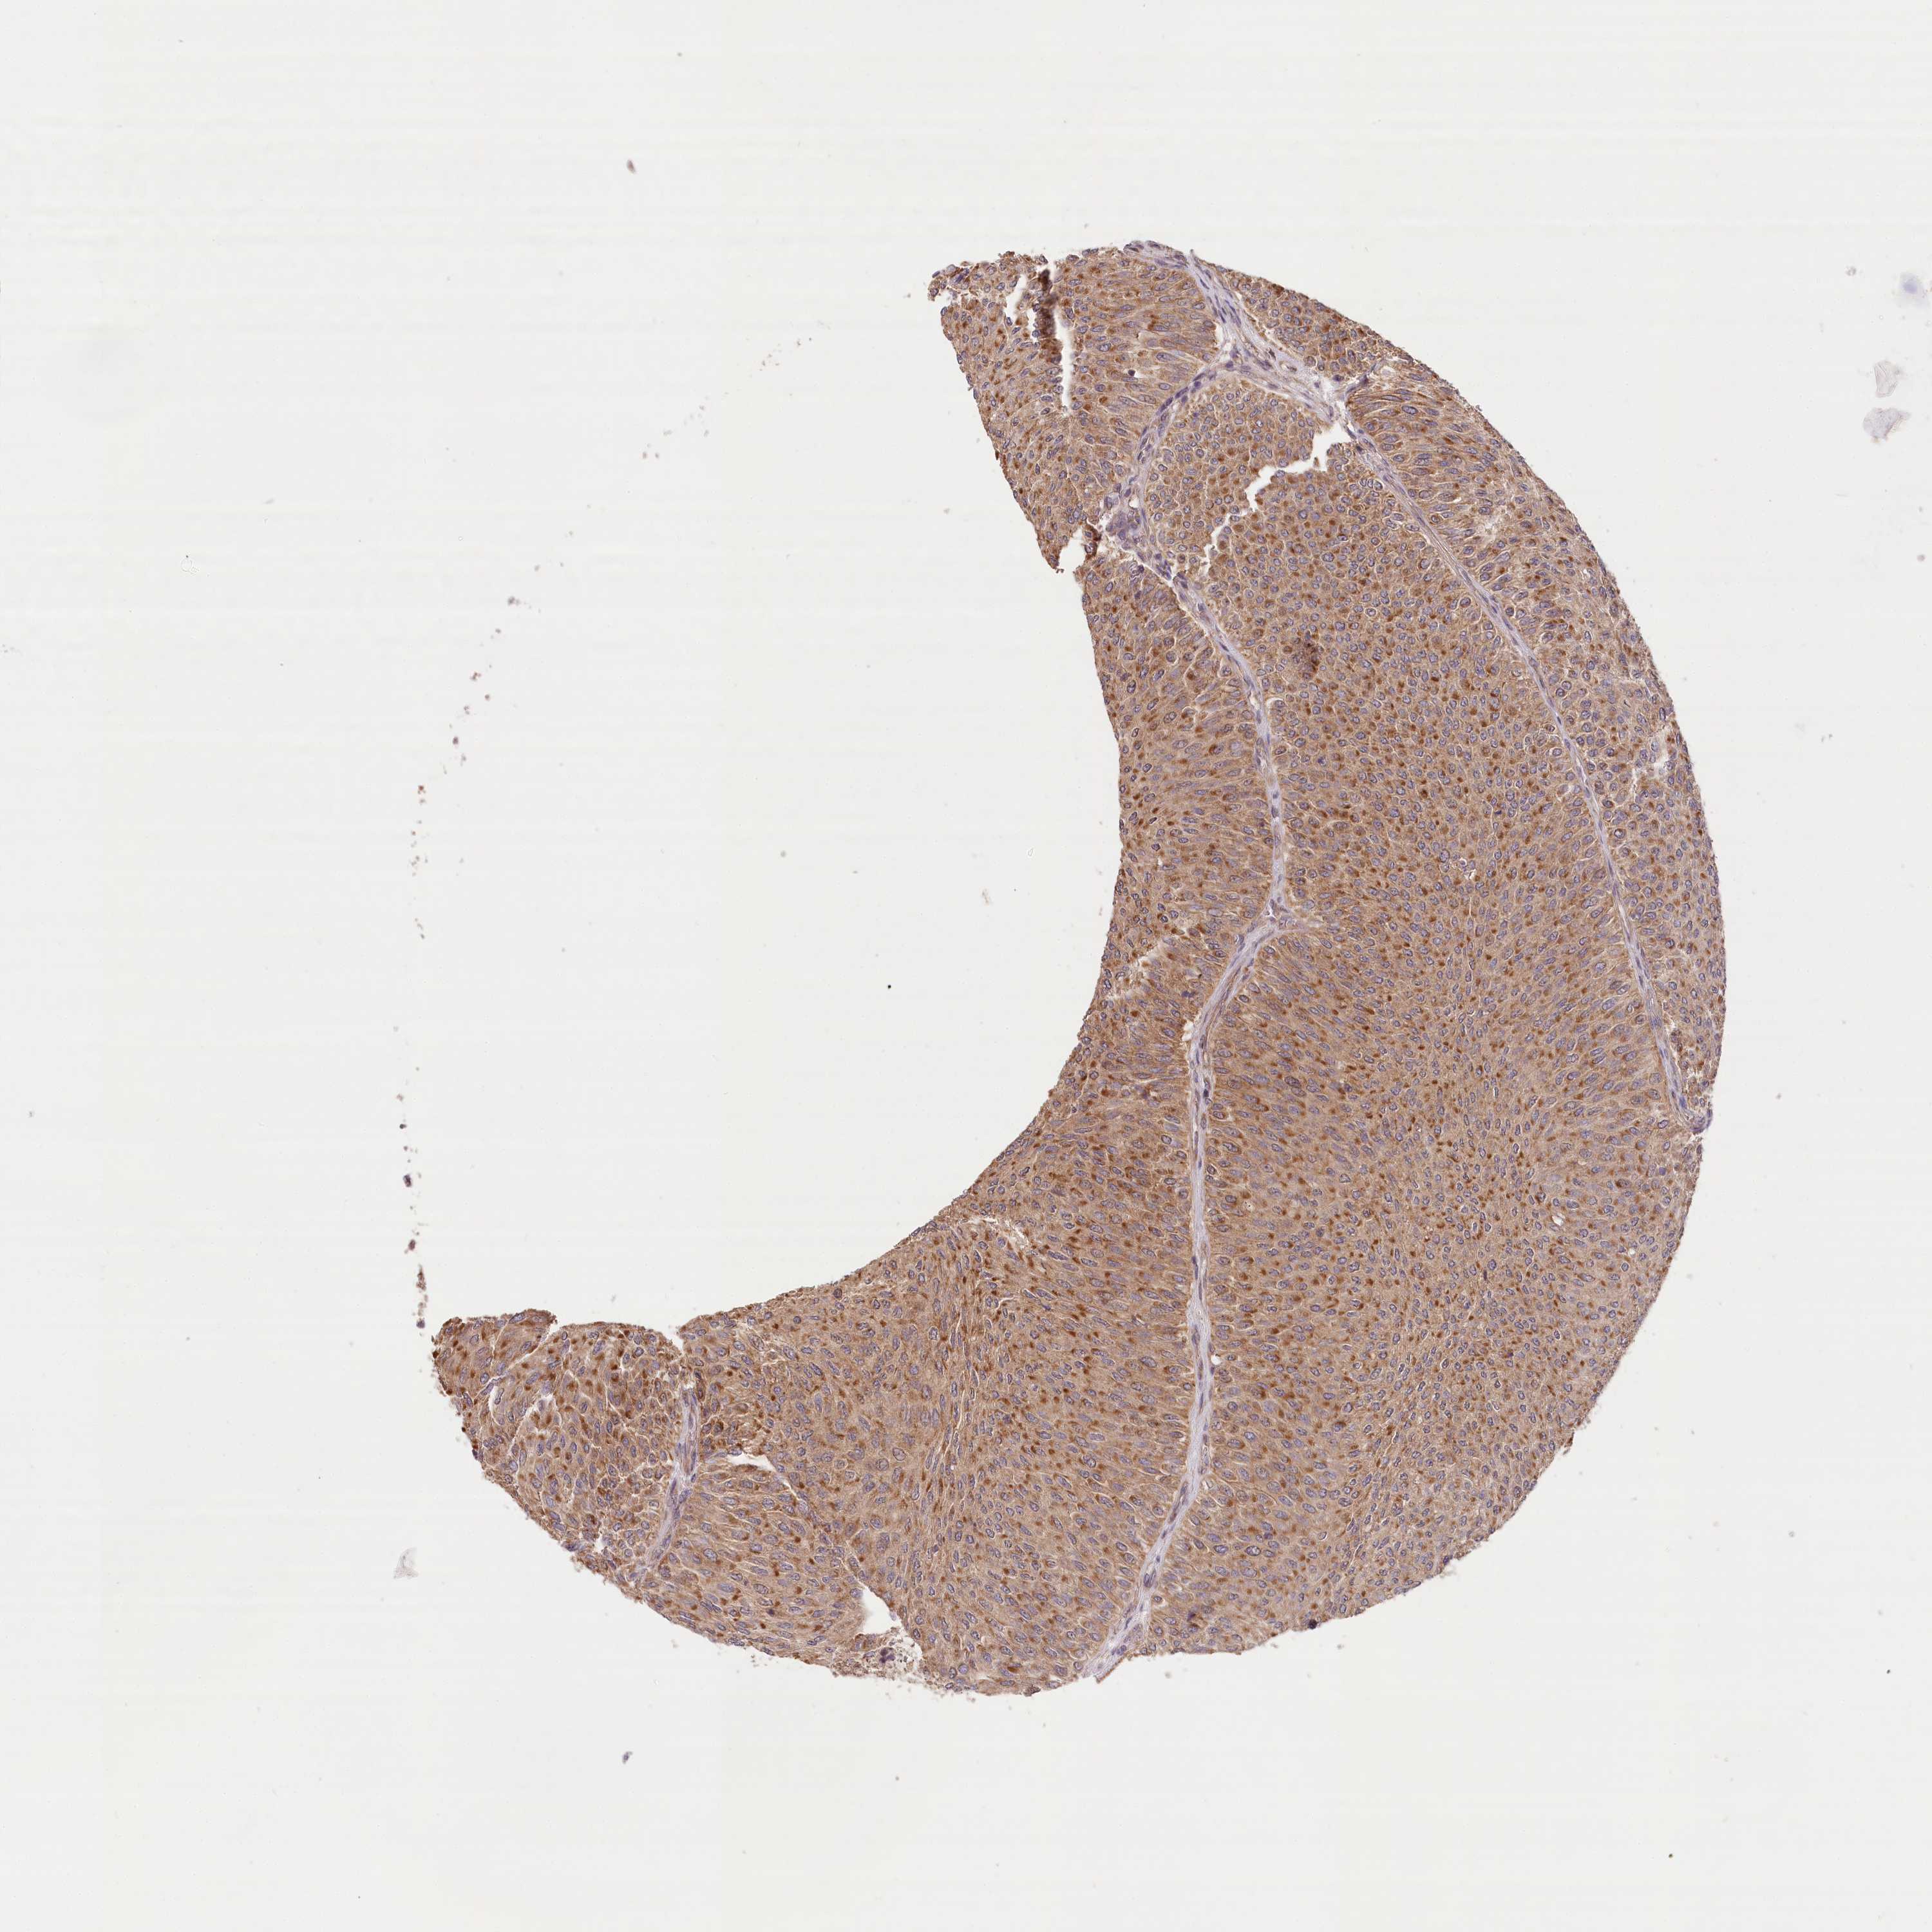

UROTHELIAL CANCER - Protein expressioni

A mouse-over function shows sample information and annotation data. Click on an image to view it in a full screen mode. Samples can be filtered based on level of antibody staining by selecting one or several of the following categories: high, medium, low and not detected. The assay and annotation is described here.

Antibody stainingi

Antibody staining in the annotated cell types in the current human tissue is reported as not detected, low, medium, or high, based on conventional immunohistochemistry profiling in selected tissues. This score is based on the combination of the staining intensity and fraction of stained cells.

Each image is clickable and will lead to virtual microscopy that enables deeper exploration of all samples and also displays staining intensity scores, fraction scores and subcellular localization as well as patient and tissue information for each sample.

Antibody HPA032060

Antibody HPA032062

Antibody CAB034116

Staining

High

Medium

Low

Not detected

Intensity

Strong

Moderate

Weak

Negative

Quantity

>75%

75%-25%

<25%

None

Location

Nuclear

Cytoplasmic/membranous

Cytoplasmic/membranous,nuclear

Urothelial carcinoma, Low grade

Urothelial carcinoma, High grade